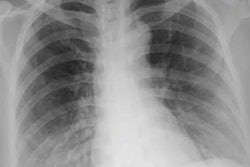

In other AI news, a machine-learning model that analyzed data from blood tests and chest x-rays was reported to be highly sensitive for identifying patients with COVID-19. The researchers even concluded that in some settings, their approach could even serve as a substitute for reverse transcription polymerase chain reaction (RT-PCR) tests.